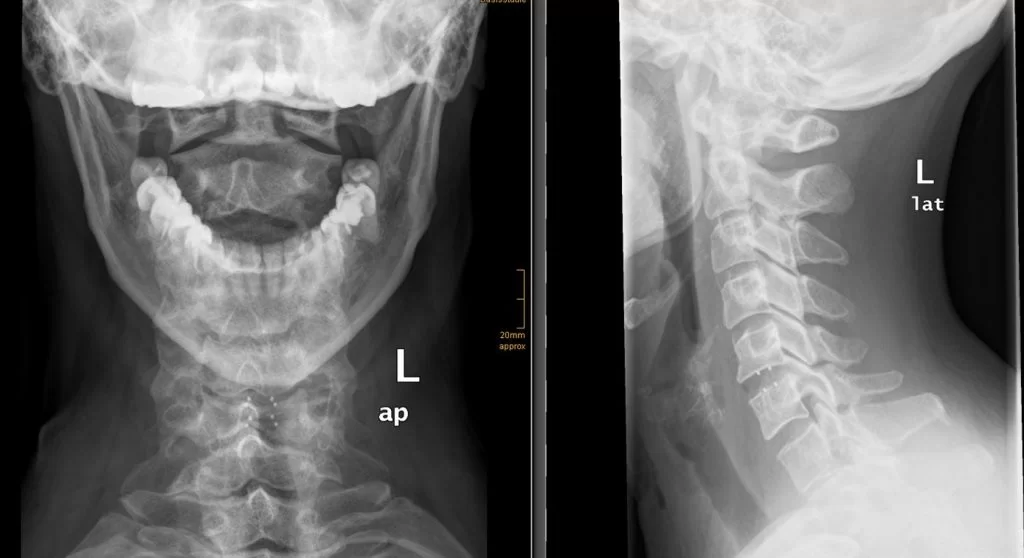

Διενεργήθη πρόσθια δισκεκτομή Α5/6 και τοποθέτηση τεχνητού δίσκου (Cadisc-C).

O ασθενής παρουσίασε άμεση βελτίωση και εξήλθε την 1η μετεγχειρητική ημέρα.

Η τοποθέτηση τεχνητού δίσκου προσφέρει το σημαντικό πλεονέκτημα της διατήρησης της κίνησης στο χειρουργηθέν επίπεδο. Όμως είναι σημαντικό η ένδειξη να είναι σωστή! Έχει ένδειξη σε νεαρά άτομα, όταν δεν υπάρχουν σημαντικές οστεοαρθριτικές αλλοιώσεις και όταν η βλάβη εντοπίζεται σε ένα επίπεδο. Πολυεπίπεδες δισκοκήλες ή εκτεταμένη οστεοφύτωση υπονοούν εκφύλιση της σπονδυλικής στήλης και σ’ αυτές τις περιπτώσεις ο τεχνητός δίσκος δεν έχει ένδειξη.